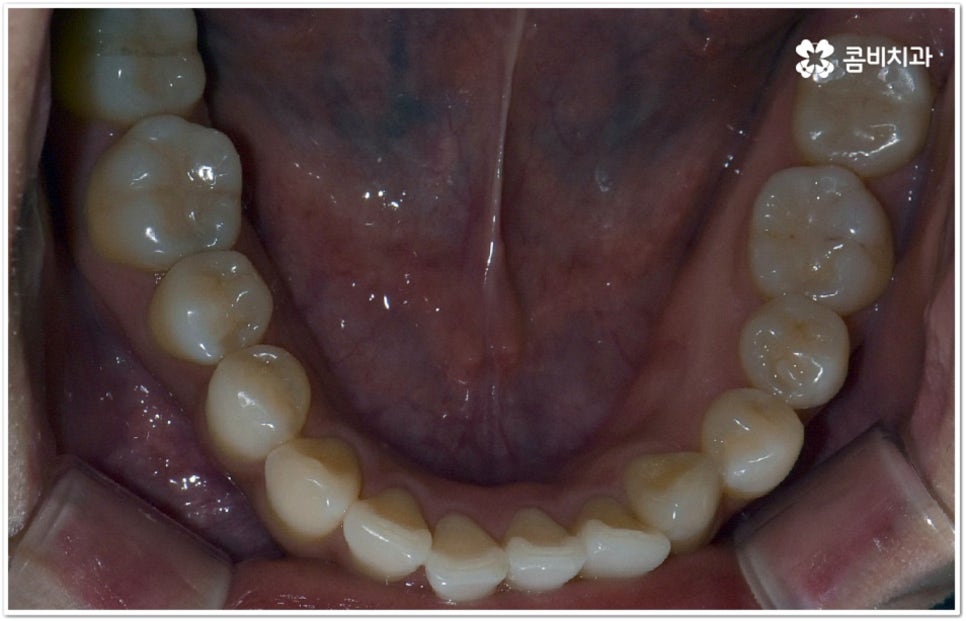

현재는 크게 불편함이 없고 환자분들의 입장에서 볼 때 스스로 교정이 딱히 필요하다고 생각되지 않는다고 해도 정밀 검진을 받아보는 것이 도움이 되는 또 다른 이유는 덧니가 생긴 원인, 구조적인 부분 등을 꼼꼼하게 체크해 봤을 때 혹시라도 추후에 치열이 더 많이 삐뚤어지거나 턱관절에 좋지 않은 영향을 줄 수 있는 상황이라면 미리 대처할 수 있다는 데 있어요. 본을 떠 보고 3D CT 를 이용해 겉으로 보이지 않는 부분까지 함께 살펴보면서 악궁 및 치아의 크기와 각도, 상악과 하악의 발달 정도 등 각자의 상황을 종합적으로 분석해 보면 앞으로의 이동 방향이나 정도 등을 어느 정도 예측해 볼 수 있는데요. 가능하다면 문제가 커진 다음에 바로잡는 것보다 지속적인 관찰을 통해 적절한 시기에 필요한 치료를 하는 것이 시간과 노력을 덜 들이는 방법이 될 거예요.

덧니의 원인에는 여러 가지가 있는데 대표적으로는 유치가 너무 일찍 빠져서 영구치가 제대로 자리를 잡지 못했거나 턱뼈의 크기와 치아 크기가 조화를 이루지 못하는 경우 등 공간이 부족한 상황을 생각해 볼 수 있어요. 덧니는 주로 송곳니가 가장 흔하나, 치열이 공간이 부족할 경우 이론적으로는 어떤 치아라도 덧니가 될 수 있어요. 이때 원인과 정도를 꼼꼼하게 파악하여 만약 해당 부위만 부분 교정이 가능하다면 덧니부분교정 치료를 할 수 있는데요. 덧니부분교정 을 이용하면 원하는 부위에만 브라켓을 부착하여 치아 이동을 시키기 때문에 전체 교정에 비해서 간편하며 치료 기간도 6~8개월 정도로 줄어들고 통증도 많이 감소될 수 있습니다. 비용적인 부담도 덜하며 (삐뚤어진 정도나 상태에 따라 다르겠지만) 보통 덧니부분교정 의 경우 비발치 과정으로 진행되기 때문에 환자분들의 입장에서는 덧니부분교정 을 많이 선호하시는 편이라고 할 수 있어요. 상황에 따라 미니스크류, 치간삭제, 악궁확장장치 등 환자에게 맞는 비발치 방법을 이용하여 도움 받을 수 있습니다.

하지만 모두에게 덧니부분교정 을 적용할 수 있는 것은 아니므로 먼저 3D CT와 같은 정밀 검사 장비를 통해서 턱의 구조적 특성 및 치열과 교합 등 구강 내부 상황에 대해 세세하게 검진을 하고 충분한 상담을 통해 각자에게 적합한 계획을 세운 다음 무리하지 않게 치료를 진행할 필요가 있어요. 만약 부분 교정을 진행할 수 없다고 해도 교정 장치를 이용하여 기간이나 통증 부분의 부담을 덜 수 있으니 너무 실망하실 필요는 없을 거예요.